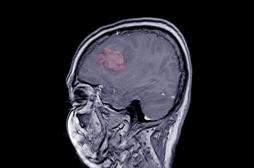

tumeur

LES MALADIES

J'AI MAL

J ai Mal Bras et mains Bras et mains Tête et cou Torse et haut du dos Jambes et pied